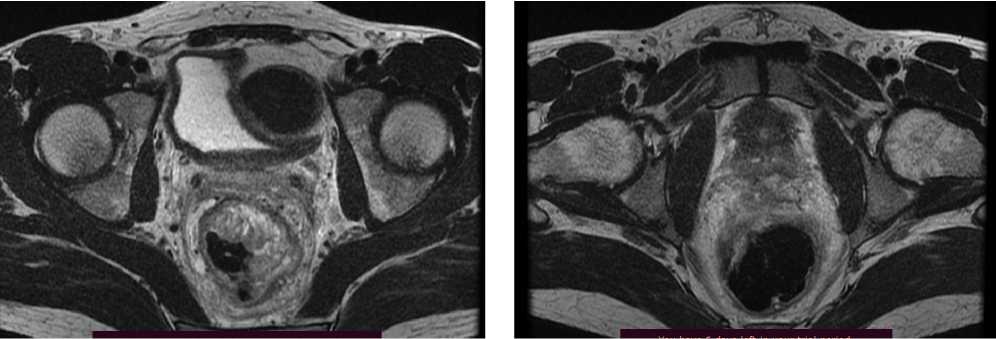

Клинический случай 3. Пациент Е., 37 лет. В июле 2022 г., в связи с дообследованием по поводу генеза кровянистых выделений из прямой кишки, выполнена ректороманоскопия, по результатам которой выявлено образование среднеампулярного отдела прямой кишки. По результатам гистологического исследования материала выявлена аденокарцинома толстой кишки, low grade.

При КТ органов брюшной полости и магнитно-резонансная томография (МРТ) органов малого таза (ОМТ) от августа 2022 г. визуализированы патологические образования в печени метастатического характера (n = 8), расположенные билобарно, и образование средне/верхнеампулярного отделов прямой кишки mrT3d/T4aN2 (CRM+ за счет прилежания лимфатического узла/EMVI+). По результатам молекулярно-генетического исследования обнаружена мутация G13D в 13 кодоне гена KRAS.

Диагноз был установлен как рак среднеампулярного отдела прямой кишки сТ4аN2M1 (hep).

По решению онкологического консилиума пациенту начат ПХТ 1 линии в режиме FOLFOX + бевацизумаб. С 02.09.2022 проведено 3 цикла ПХТ 1 линии, по результатам контрольных обследований зарегистрировано прогрессирование процесса за счет роста образований печени до 64 × 46 мм и появления линзовидного образования между передней поверхностью прямой кишки и задней поверхностью предстательной железы размерами 47 × 15 × 25 мм (рис. 7, 8).

Рис. 7. Результаты компьютерной томографии органов брюшной полости у пациента 37 лет с диагнозом метастатический колоректальный рак с признаками микросателлитной нестабильности (октябрь 2022 г., после 3-х циклов FOLFOX + бевацизумаб)

Fig. 7. Results of abdominal CT scan in a 37-year-old patient diagnosed with metastatic MSI-H colorectal cancer (October 2022, after 3 cycles of FOLFOX + bevacizumab)

Рис. 8. Результаты магнитно-резонансной томографии органов брюшной полости у пациента 37 лет с диагнозом метастатический колоректальный рак с признаками микросателлитной нестабильности (октябрь 2022 г., после 3-х циклов FOLFOX + бевацизумаб)

Fig. 8. Results of abdominal MRI in a 37-year-old patient diagnosed with metastatic MSI-H colorectal cancer (October 2022, after 3 cycles of FOLFOX + bevacizumab)

В октябре 2022 г. получены результаты иммуногистохимического исследования на предмет MSI, выявлена утрата ядерной экспрессии MLH1 и PMS2.

С учетом результатов ИГХ, прогрессирования процесса по результатам контрольных обследований, пациенту начата 2 линия системного лечения пембролизумабом в монорежиме.

С ноября 2022 г. выполнено 14 введений пембролизумаба с максимальным эффектом частичный регресс (образование между передней поверхностью прямой кишки и задней поверхностью предстательной железы регрессировало полностью). По результатам контрольных обследований (КТ ОБП и МРТ ОМТ от сентября 2023 г.) сохраняются очаги в печени до 21 × 11 мм, а также опухоль средне- и верхнеампулярного отделов прямой кишки с выраженным муцинозным компонентом. МР-стадия Т4а (CRM+, EMVI+) (рис. 9, 10).

Рис. 9. Частичный регресс, по данным компьютерной томографии органов брюшной полости, на фоне иммунотерапии пембролизумабом у пациента 38 лет с диагнозом метастатический колоректальный рак с признаками микросателлитной нестабильности (сентябрь 2023 г.)

Fig. 9. Partial response according to abdominal CT scan data during immunotherapy with pembrolizumab in a 38-year-old patient with metastatic MSI-H colorectal cancer (September 2023)

Рис. 10. Частичный регресс, по данным магнитно-резонансной томографии органов брюшной полости, на фоне иммунотерапии пембролизумабом у пациента 38 лет с диагнозом метастатический колоректальный рак с признаками микросателлитной нестабильности; МР-стадия Т4а (CRM+, EMVI+) (сентябрь 2023 г.)

Fig. 10. Partial response according to abdominal magnetic resonance imaging during immunotherapy with pembrolizumab in a 38-year-old patient diagnosed with metastatic MSI-H colorectal cancer; MR stage T4a (CRM+, EMVI+) (September 2023)